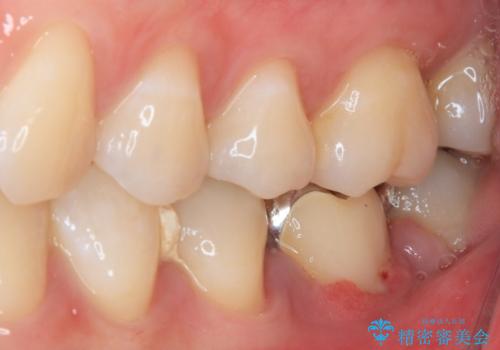

- ブリッジの歯のないところにインプラントを入れて、銀歯を白くやり替えたいと来院された患者様です。

歯の欠損している箇所にはインプラント治療をし、銀歯と仮詰めの部分はセラミックインレーにて補綴することとしました。

すべての治療の前に親知らずの抜歯も行っています。